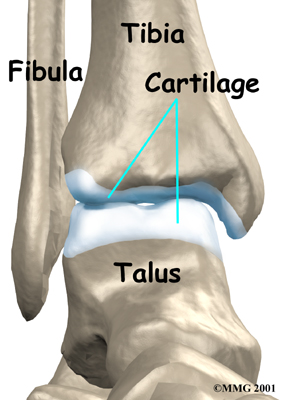

The ankle joint is made up of three bones: the lower end of the tibia (shinbone), the fibula (the small bone of the lower leg), and the talus (the bone that fits into the socket formed by the tibia and fibula).

Inside the joint, the bones are covered with a slick, smooth material called articular cartilage. Articular cartilage is the material that allows the bones to move against one another in the joints of the body. The cartilage lining is about one-quarter of an inch thick in most joints that carry body weight, such as the ankle, hip, or knee. It is soft enough to allow for shock absorption but tough enough to last a lifetime, as long as it is not injured.